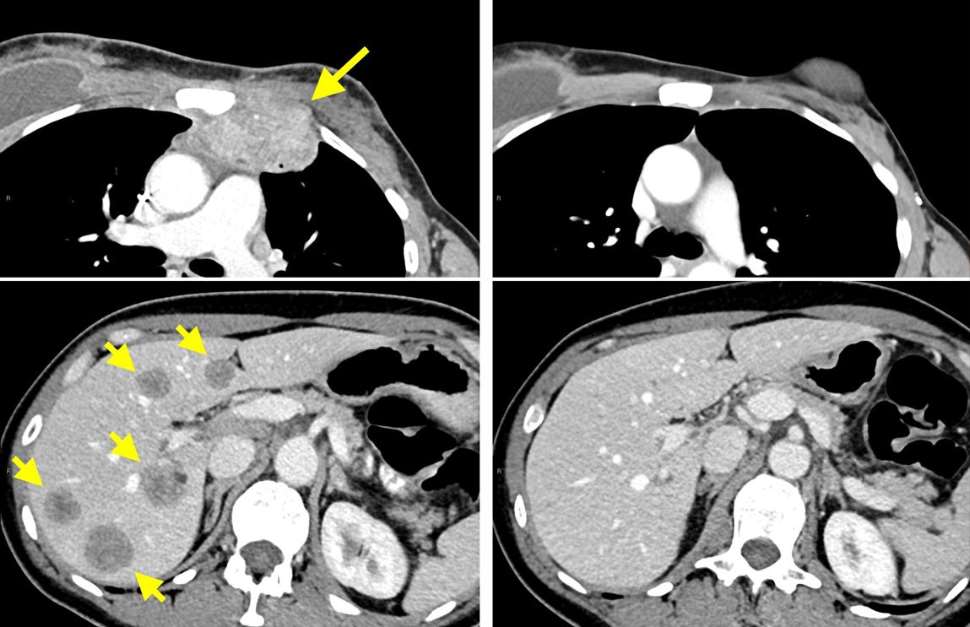

Respuesta de la paciente a la inmunoterapia. A la izquierda está la imagen del tórax y el hígado antes del tratamiento, con flechas amarillas que apuntan a los tumores. A la derecha, sin tumores tras 14 meses de terapia. Foto cortesía de National Cancer Institute

Esta semana la revista Nature Medicine ha publicado el exitoso caso de una mujer de 49 años con cáncer de mama metastásico HER2 negativo –contra el que no funcionaron distintos regímenes de quimioterapia–, que se inscribió en un ensayo clínico diseñado para mediar la regresión del tumor en pacientes con cánceres epiteliales que desarrollan metástasis.

En este trabajo, los científicos aislaron y reactivaron las células T de esta paciente cuyo cáncer de mama metastásico estaba progresando a pesar de las terapias utilizadas.

Estas células T reactivadas eliminaron todas las lesiones metastásicas, dejando libre de enfermedad a la mujer tras dos años desde el tratamiento.